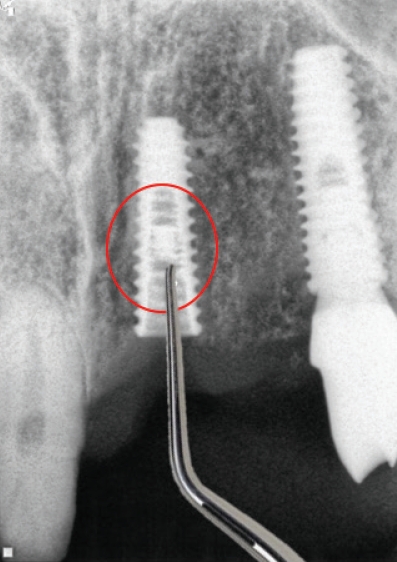

Fig. 7.

Bur를 이용하여 지대주파절편제거하기

연결나사의 파절보다 빈발하게 발생하는 것이 지대주의 파절인데(Fig. 5) 제거가 잘 되지 않는다. 이때는 다양한 방법으로 제거를 할 수 있으나 최근에는 여러 회사에서 발매되어 나오는 리무버가 있어 제거가 비교적 용이해졌다(Fig. 6).

리무버를 적용할 때 주의할 사항은 역회전으로 고정을 하여야한다는 것이다. 이후에 라쳇이나 토크렌치등으로 잡고 흔들어서 제거해야만 제거가 용이하다. 그럼에도 불구하고 제거에 실패하는 경우에는 bur를 이용하여여 제거하는 수 밖에 없다(Fig. 7).